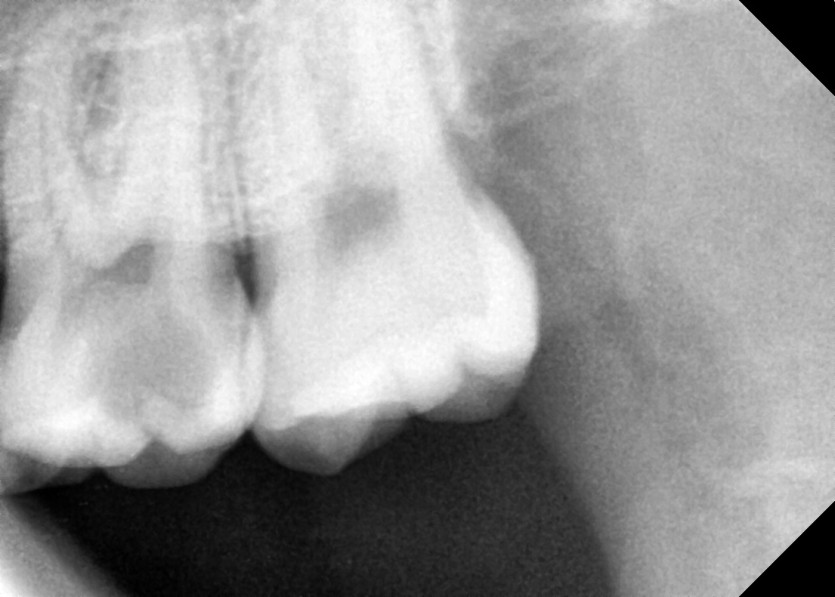

#28,38 사랑니 발치

구강 외과 전문의가 당일 발치했습니다.